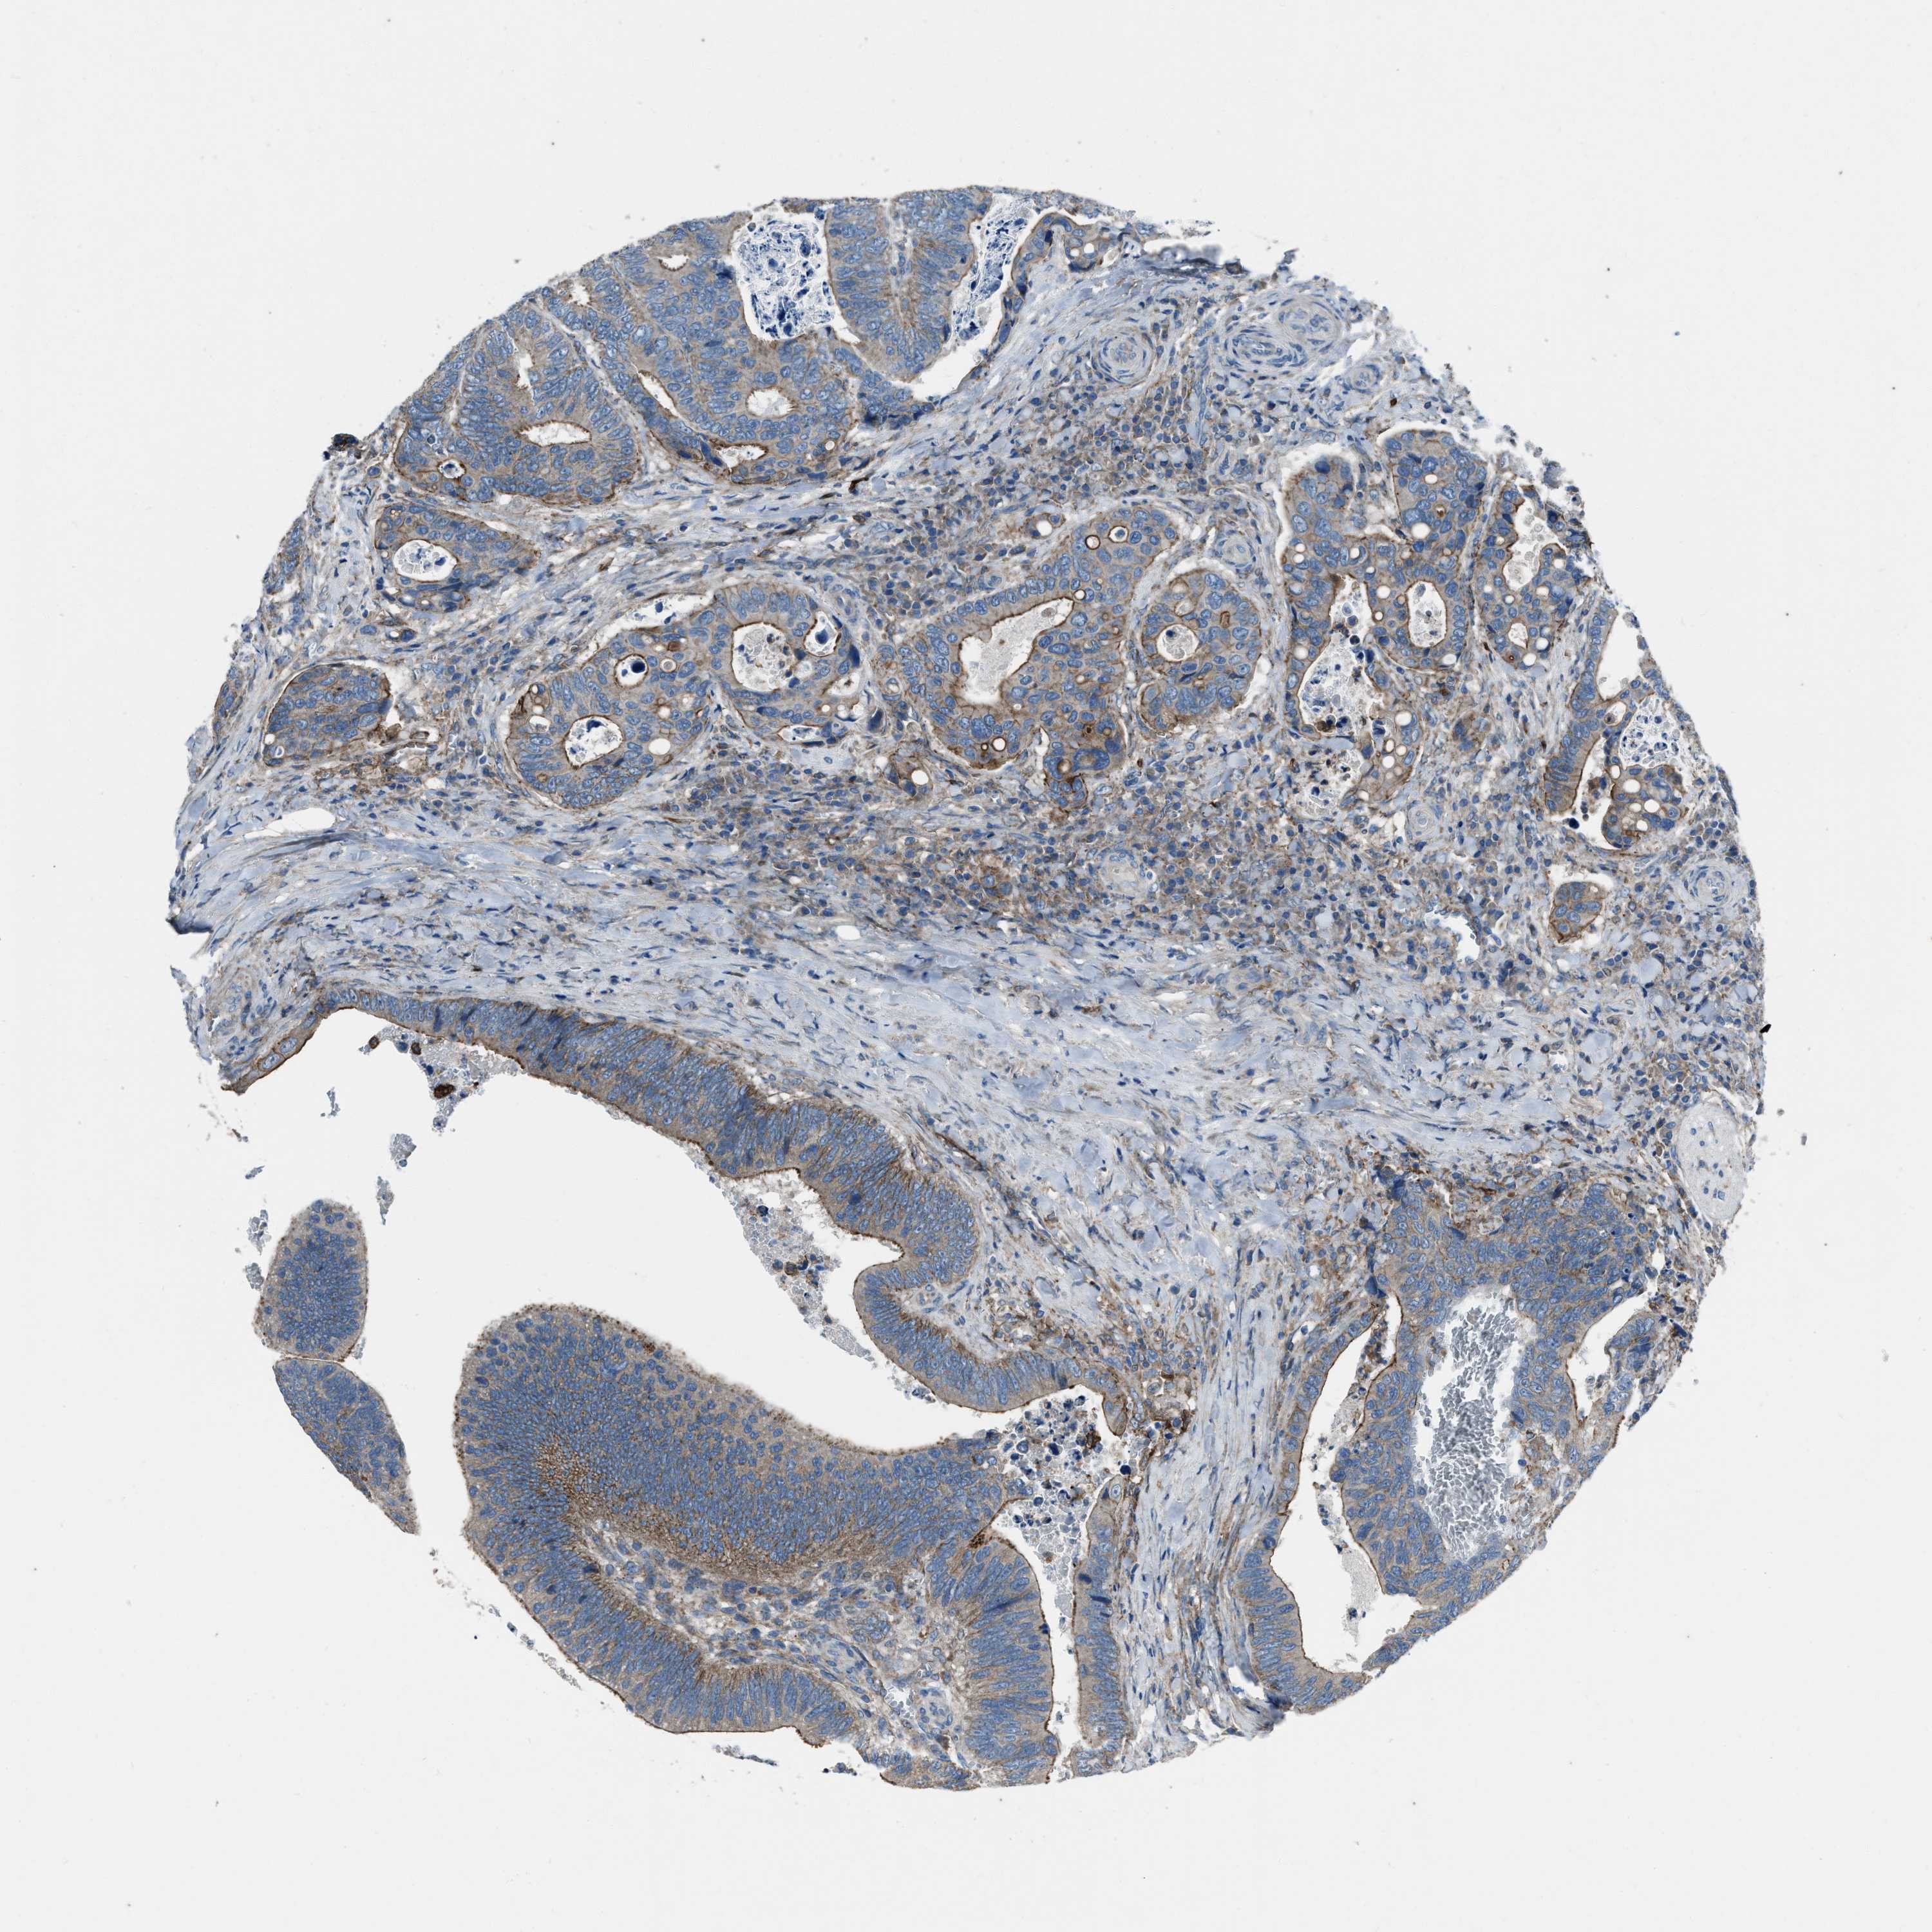

CANCER COLORECTAL CANCER Show tissue menu

COAD TCGA COAD VALIDATION READ TCGA READ VALIDATION PROTEIN COAD CPTAC PROTEIN EXPRESSION

ANTIBODIES

AND

VALIDATION